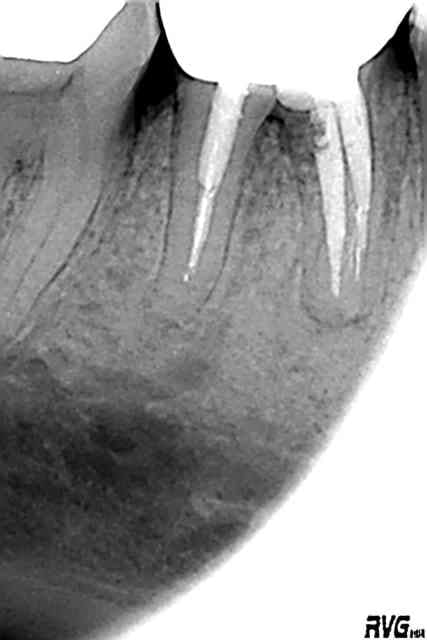

Avant 24062003 ex7dhe - Eugenol

Apres 25022005 blbnb9 - Eugenol

Al tu exagères, tu as inversé les radios.

Je te jure que c'est vrai. La date dans le nom des radios est exacte.

J'e ne suis moi-même, pas encore revenu de ce succès, alors que je n'avais apparemment pas obtenu la perméabilité apicale.

Mais j'ai irrigué, irrigué et encore irrigué, à la seringue d'hypochlorite.

Ensuite condensation verticale à la gutta chaude. Et voilà le résultat.